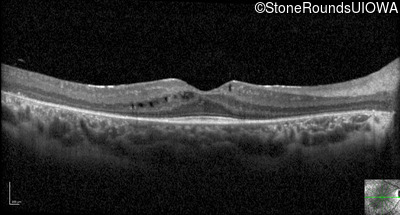

Optical Coherence Tomography - Left - 20/32

Exemplar / OCT Stack

OCT Stack